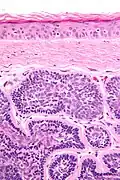

Dermal cylindromas are:

- Dermal lesions consisting of nests of cells that are surrounded by hyaline (i.e., glassy, eosinophilic, acellular) material and have:

- Hyperchromatic nuclei that may palisade (columnar nuclei arranged around the periphery of the cell nests with their short axis tangential to the nest periphery), and

- Cells with lighter staining ovoid nuclei at their centre.

They lack of a significant number of lymphocytes; this differentiates them from spiradenomas.

Micrograph of a dermal cylindroma in H&E stain. -

Micrograph of dermal cylindroma in H&E stain. -